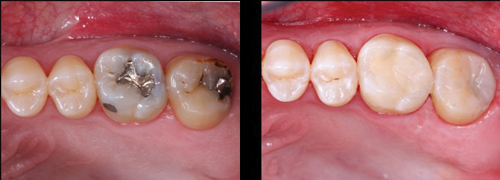

Bulk filling of tooth preparations for composite resin was initiated a few years ago, and it is now suggested by most resin companies. The proposed advantages were that the bulk-fill technique saved time and was easier than placing resin in small 1 mm to 2 mm increments (figure 1). Many dentists changed to bulk filling and enjoyed success. But many dentists have changed back to the incremental placement techniques after encountering challenges with the bulk-fill technique. It is my observation from my many CE presentations that the majority of dentists are again using the incremental placement procedure.

Figure 1: Most dentists place large Class II resin-based composite restorations routinely. However, their clinical longevity has been shown to be only several years. The size of many of these restorations has motivated dentists to place large quantities of resin all at once. This technique can be very good or significantly problematic, depending on how it is accomplished. Note the presence of slight "white lines" on the first molar margins caused by overfinishing the restoration.

Figures 2a and 2b: Small Class II resin-based composite restorations can often be filled in bulk successfully if the matrix is placed adequately, the light used is powerful enough, and the light is aimed correctly and as close to the resin as possible.